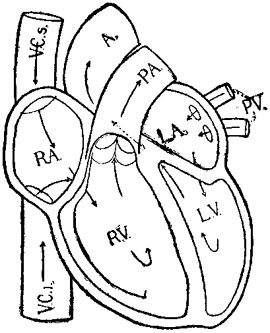

118 The Blood-Route trought the Heart

facing 110 Diagram of the Circulatory System